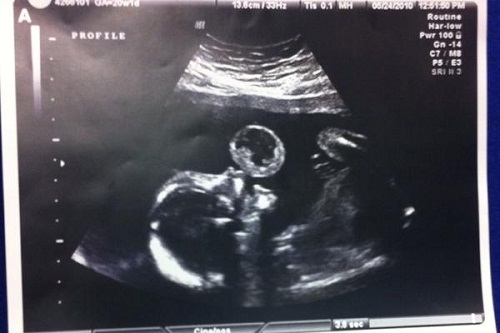

Qua siêu âm cho một bà mẹ ở Mỹ mang thai 17 tuần, các bác sĩ phát hiện thai nhi đang “thổi bong bóng” rất đáng yêu. Tuy nhiên, sự thật phía sau khiến bà mẹ kinh hãi.

Chị Tammy Gonzales, ở Florida, Mỹ, đi siêu âm khi mang thai được 17 tuần. Qua siêu âm, các bác sĩ nhìn thấy hình ảnh thai nhi thổi ra một bong bóng to nhìn có vẻ rất đáng yêu nhưng sự thật lại kinh hãi vô cùng.

Theo đó, các bác sĩ cho biết, thai nhi không phải đang thổi bong bóng mà là một dạng khối u rất hiếm gặp.

Qua siêu âm các bác sĩ phát hiện thai nhi có khối u hiếm gặp, nhìn qua cứ nghĩ như đang "thổi bong bóng" |